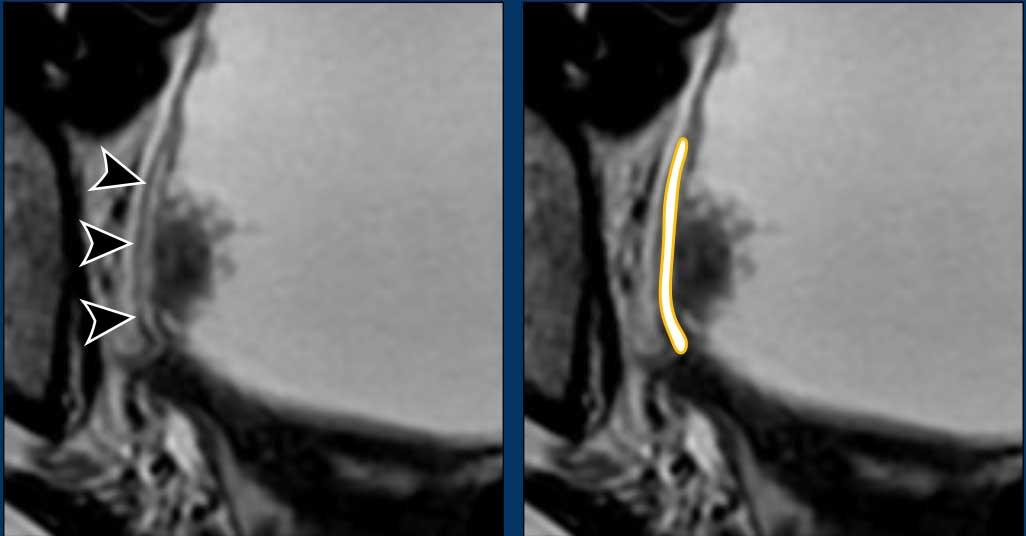

Đây là ví dụ về phù nề lớp trong trên hình ảnh chuỗi xung T2W.

Phù nề có tín hiệu cao trên T2W nhưng nước tiểu cũng vậy.

Tuy nhiên vì phù nề nằm trong thành bàng quang nên có thể phân biệt được.

Trên hình ảnh DCE, lớp trong phù nề có thể biểu hiện ngấm thuốc sớm do tình trạng xung huyết (đầu mũi tên).